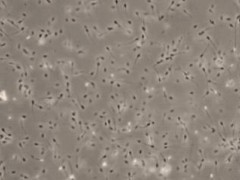

人的免疫细胞(PBMC)分离和冻存方案

一文了解细胞冻存知识

细胞长期冻存,会影响细胞活性吗?

干货分享 | 细胞冻存与复苏避坑指南 ( 不看后悔 !!!)

科普 | 5分钟学会细胞冻存技术